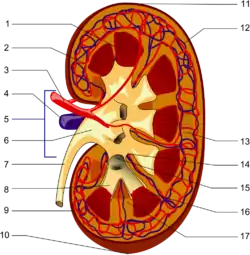

Renal papilla Frontal section through the kidney